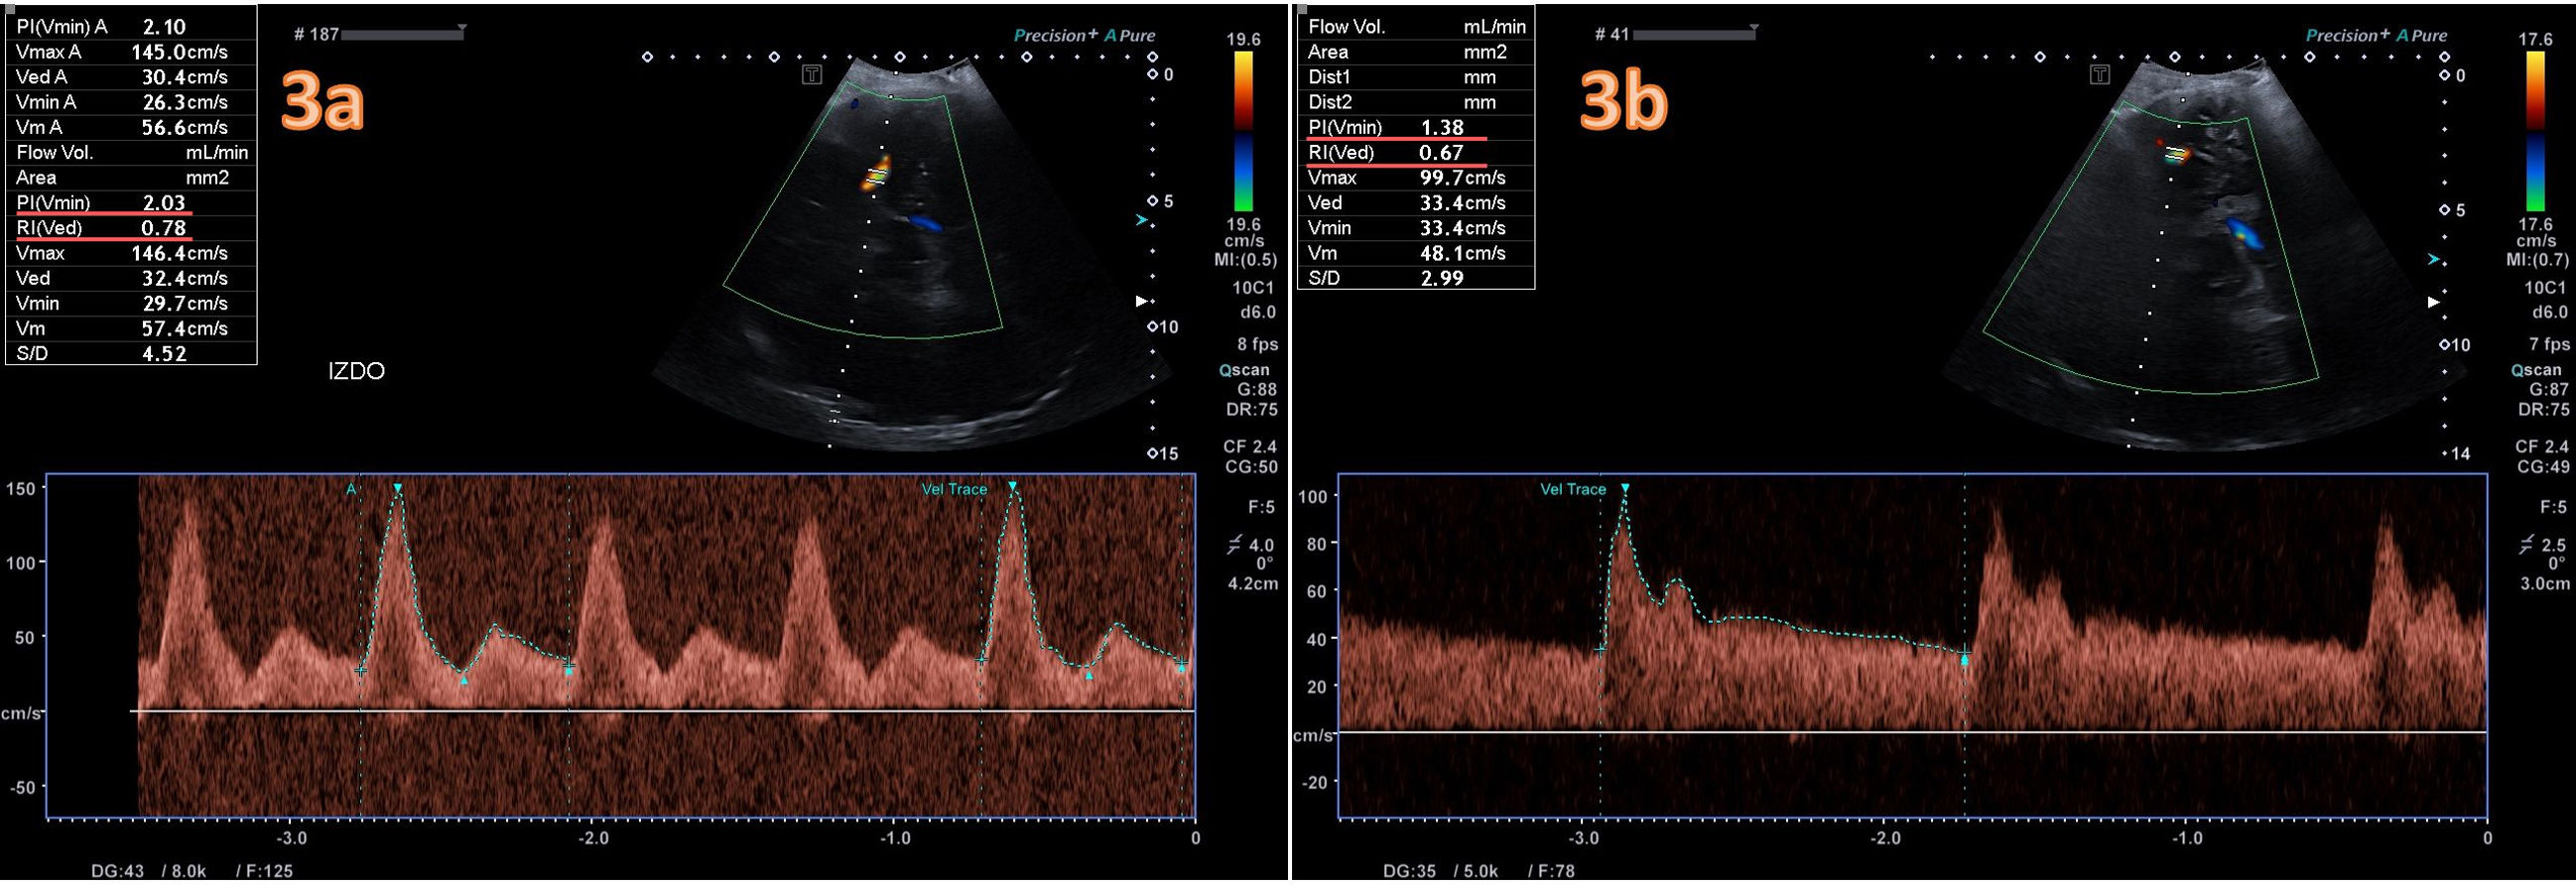

3a) Doppler transcraneal del flujo de arteria cerebral media izquierda a través de la ventana transtemporal al diagnóstico. Trazado patológico inicial con IP 2,1, e IR 0,78 que sugieren elevada PIC. 3b) Medición a los 5 días de tratamiento con cambio en el trazado y disminución de ambos índices, IP 1,38, e IR 0,67.